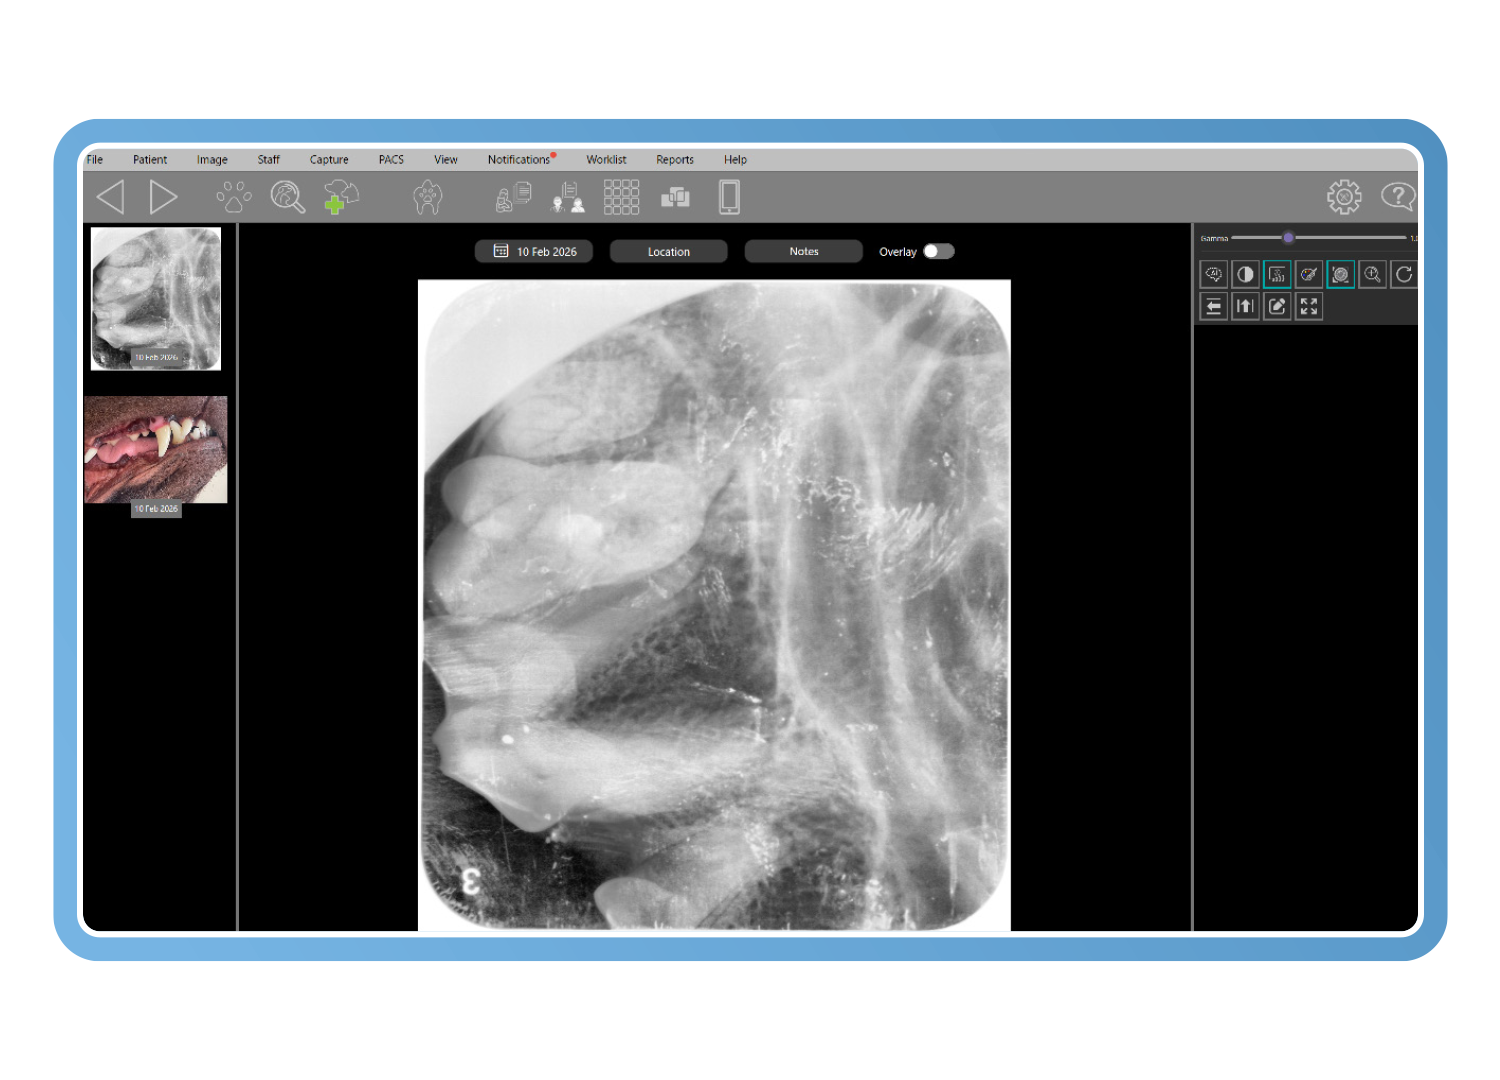

Herramientas diagnósticas específicas para veterinaria

Las herramientas avanzadas de imagen veterinaria mejoran el detalle diagnóstico incluso a partir de imágenes subóptimas. El análisis de Clarity detecta cambios con una diferencia de contraste de tan solo un 2 %, mientras que los filtros inteligentes y la visualización en pseudocolor revelan la pérdida ósea y los detalles periodontales, reduciendo las repeticiones y convirtiendo imágenes de baja calidad en imágenes diagnósticas.